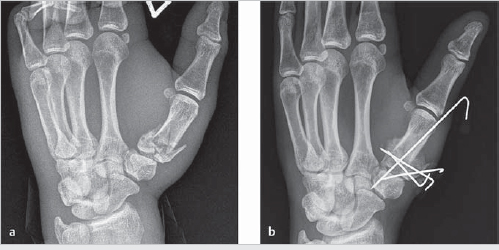

Fractures can be extra-articular, intra-articular with a stable volar-ulnar fragment (a Bennett’s fracture), or intra-articular with comminution (a Rolando’s fracture, see ► Fig. 6.1a).

Operative: If unstable or intra-articular, then proceed with open reduction internal fixation (ORIF) versus closed reduction percutaneous pinning (CRPP) (► Fig. 6.1b).